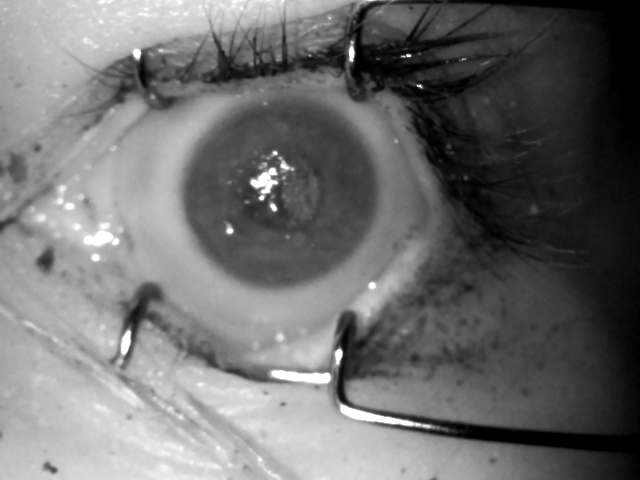

Following the findings reported in [7] that strongly favor the NIR images for post-mortem iris recognition purposes, we only employ this type of images in all experiments conducted in this work. Example images from each of the evaluation databases are shown in Fig. 1.

In addition to the model described above, in this work we have implemented and trained two additional models, ending up with three models in total, which are detailed below and their example predictions given in Fig. 2

OSIRIS segmentation, normalized images, and normalized masks

coarse CNN binary predictions with fitted Hough circles, segmented images, normalized images, and normalized masks

fine and fine v2highres CNN segmented images, normalized images, and normalized masks

4.3 Iris and mask normalization

For the proposed method to serve as a drop-in replacement for the Daugman method recognition pipeline, the prediction obtained from the DCNN-based segmentation has to be correctly normalized onto a dimensionless polar-coordinate rectangle. For this stage, a method for localizing pupillary and limbic iris boundaries has been devised, which employs a Hough transform that is applied to the prediction obtained from the coarse segmentation model, similarly to the methodology introduced in [21] and [22], as this model yields the smoothest prediction. These boundary parameters are then used in all subsequent experiments, including those involving the fine and fine v2highres models. The segmentation methodology employing the coarse segmentation model is visualized in Fig. 2. Similar results are then presented in Fig. 3 for the two remaining fine-grained models. Notably, the original fine model from [10] seems to over-aggressively mask out some portions of the iris, while at the same time mistakenly denoting some portions of the pupil as iris. This is fixed in the fine v2highres model, which was trained with twice the iterations count, cf. right side of Fig. 3.